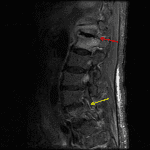

- T2/STIR signal hyperintensity, T1 signal hypointensity, and enhancement in the T12-L1 disc and in the majority of the T12 and L1 vertebral bodies extending into the pedicles bilaterally

- Surrounding T2/STIR hyperintensity and enhancement in the paraspinal soft tissues and superior aspects of the psoas muscles without peripherally-enhancing collection

- T2/STIR signal hyperintensity and enhancement in the left L4-L5 facet joint, the adjacent articular pillars, and in the surrounding soft tissues with multiple subcentimeter peripherally-enhancing collections in the L4-L5 interspinous ligament and posterior paraspinal soft tissues

- Epidural enhancing soft tissue at the level of L5 with a 1 cm peripherally-enhancing collection in the right dorsal epidural space at this level

- Multilevel degenerative disc and facet disease with discogenic endplate degenerative changes. The combination of broad-based disc bulges, facet hypertrophy, and ligamentum flavum thickening contribute to advanced spinal canal stenosis at L3-L4, moderate spinal canal stenosis at L4-L5, and multilevel neural foraminal stenosis, which is advanced on the right at L3-L4

Discitis/osteomyelitis, septic facet arthritis, and epidural abscess

Findings consistent with left L4-L5 septic facet arthritis with associated osteomyelitis involving the adjacent articular pillars and surrounding phlegmon with intermixed scattered subcentimeter posterior paraspinal abscesses. Contiguous epidural phlegmon at the level of L5 with a 1 cm epidural abscess in the right dorsal epidural space.

T12-L1 discitis/osteomyelitis. Surrounding paraspinal phlegmon without evidence of epidural or paraspinal abscess at this level.

Multilevel degenerative changes with the combination of broad-based disc bulges, facet hypertrophy, and ligamentum flavum thickening contributing to advanced spinal canal stenosis at L3-L4, moderate spinal canal stenosis at L4-L5, and multilevel neural foraminal stenosis, which is advanced on the right at L3-L4.